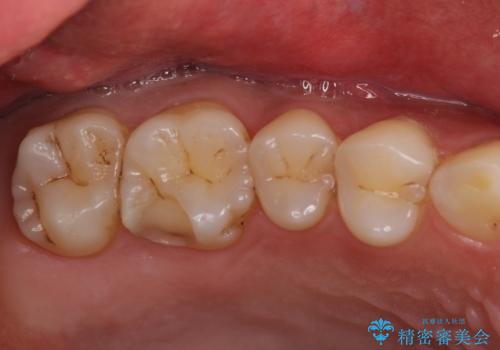

- つめものが欠けたことを主訴にご来院された患者様です。

以前、日本で保険治療をしていましたが、米国滞在中にとれて、仮の再治療をしました。その際に、中に虫歯が残っていると笑われたそうです。

今回は虫歯が大きかったものの、ぎりぎり神経に達しておらず、セラミックインレー(つめもの)の治療のみで完了しました。初診時に虫歯を除去し、後日神経のテストをして正常反応を確認しました。